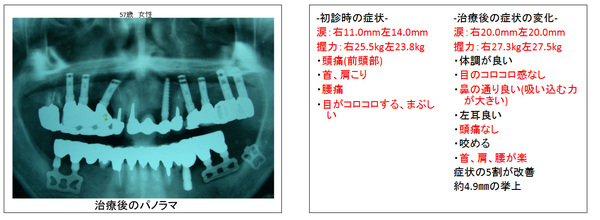

インプラント治療後の噛み合わせ治療の症例

他院でインプラント治療後に再度噛み合わせ治療をした3症例

インプラントの埋入は、大きく分けて、部分的に失った場所に少数のインプラントを埋入することで他の歯を削らなくて歯が固定されるケースと多数のインプラントを埋入することで義歯から解放され、固定ブリッジになるケースが考えられます。

すなわち、噛み合わせが低くなることで、噛み合わせのバランスが崩れ全身的に見て顔貌、姿勢は歪み、自律神経は乱れ、免疫力、ホルモン力も低下を来しその結果、健康をも害しているのです。

インプラントの固定する数ヶ月の間の仮歯を用いて、噛み合わせ治療を行い、高くなる事でいかに健康を取り戻すことが出来るかということを自分の身体で体感して、診断するのです。

そして、自分の健康に適する顎の位置でブリッジなり、義歯を作ることで審美的にも機能的にも満足され、なおかつ健康を取り戻すことが出来るのです。